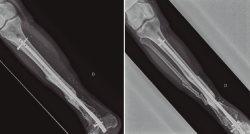

Figura 4. Una vez confirmada la erradicación de la infección, se procedió a la retirada del fijador externo. Se realizó un aporte de injerto óseo autólogo procedente de la tabla interna de la tibia y una posterior fijación interna de la fractura mediante una artrodesis de tobillo. El resultado final fue una correcta consolidación de la fractura.